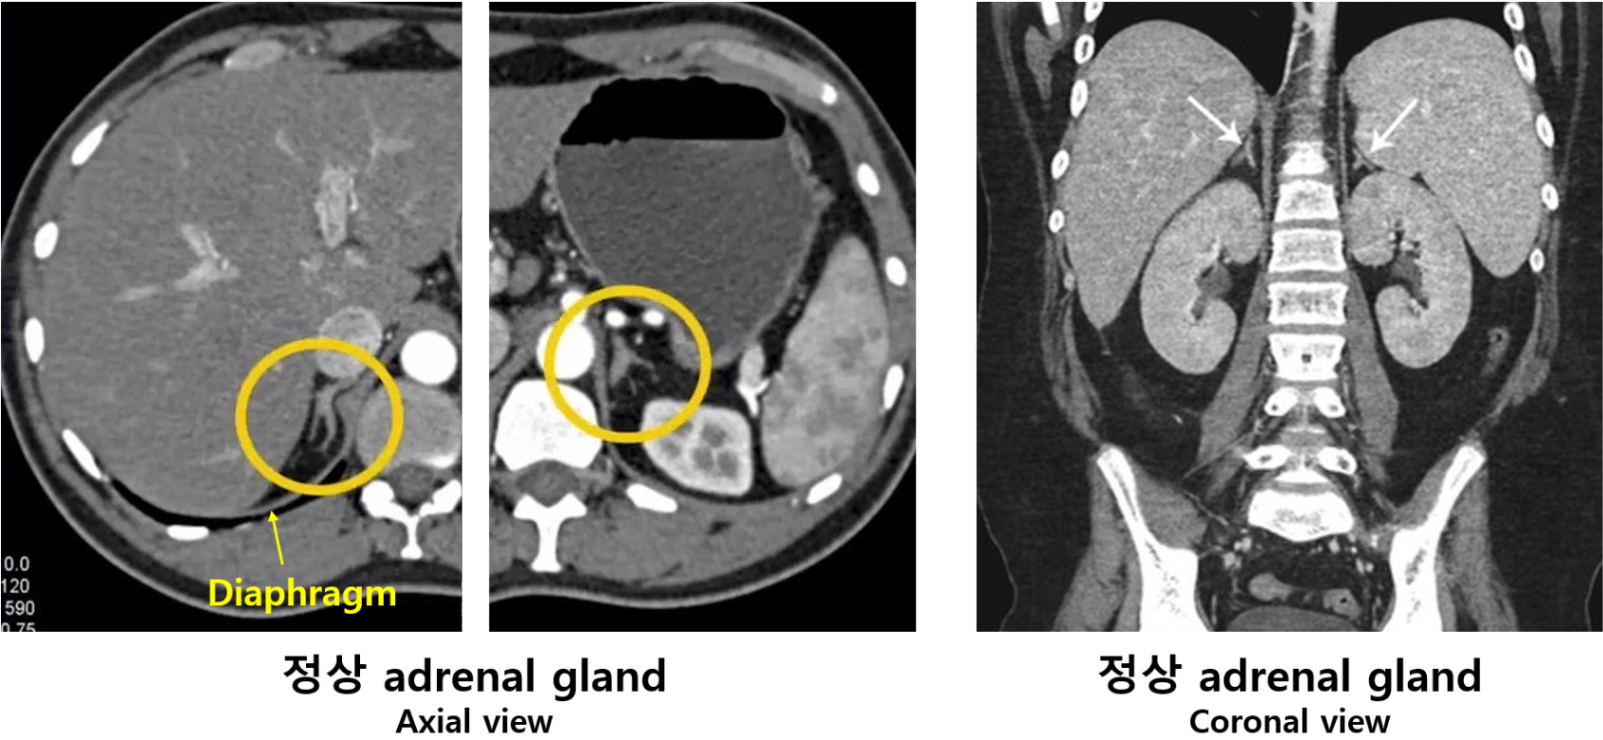

1) 해부학적 위치: 신장 위에 위치

(1) 부신: Inverted Y (ㅅ) 모양

(2) Adrenal gland의 정상 두께는 diaphragm 두께보다 약간 두꺼움

* CT 상 정상 부신의 위치, 모양이 어떤지 꼭 숙지해야 한다.